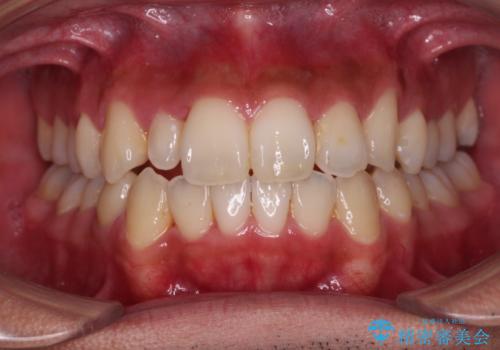

【モニター】左右のクロスバイトをインビザラインできれいに改善

- 前歯のデコボコとクロスバイトを気にして来院された患者様です。

下顎の歯列弓に対して上顎歯列弓がやや小さく、側方の歯を中心にクロスバイトが見受けられました。

奥歯の咬み合わせは接触が少なく物足りないように見えますが、患者様としては十分に咬むことができるとのことでした。